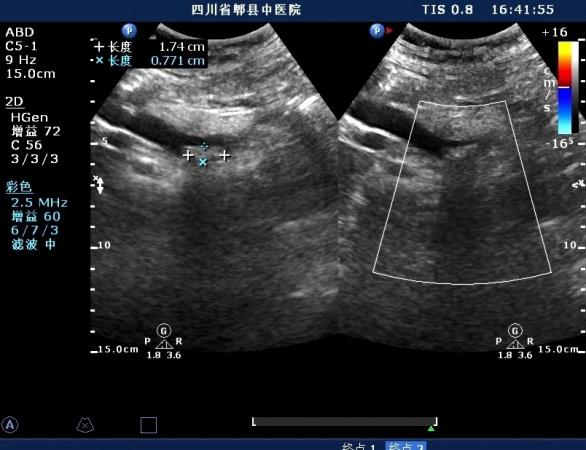

超声如图:胆总管及肝内胆管扩张,呈“平行管征”,胆总管胰腺段可见疏松强回声团堆积,后方可见淡淡声影,左肝外叶胆管内亦可见数个强回声团堆积,后方伴声影。 肝脏及胆总管

扩张的胆总管

扩张的右肝内胆管